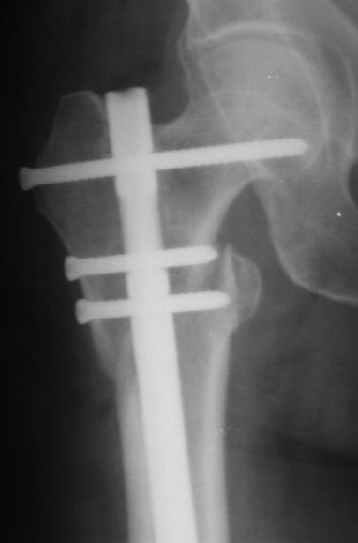

В частности, на проксимальном конце сделано еще одно дополнительное статическое отверстие. Можно ввести в проксимальном отделе 4 винта, из них 3 статические (2 в круглые отверстия и 1 по нижнему краю овального). Картинки в приложении. На дистальном конце стержня тоже кое-что улучшено. Спрашивайте в аптеках, как говорится. Выпускается предприятием "ЦИТО" (Москва), то есть это малобюджетное решение.

В частности, его возможности при фиксации переломов проксимального отдела бедра - в сравнении с другими, имеюшими лишь по одному статическому и динамическому отверстию и с кондуктором для введения 2 винтов.

Это было года 2,5 назад, мы тогда еще уточняли возможности шинирования с угловой стабильностью гвоздем с поперечным расположением винтов при переломах проксимального отдела бедра. Пациенту не пришлось приобретать намного более дорогой рекон или проксимальный гвоздь. В приложении еще несколько примеров применения того гвоздя при высоких переломах бедра, в том числе с более латеральной точкой входа. Гвоздь изгибаем для этого.